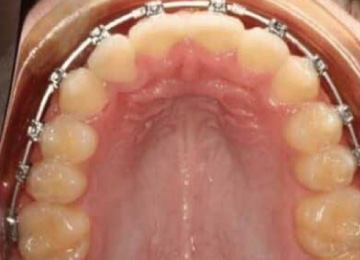

Одним из эффективных методов исправления прикуса у подростков после прорезывания зубов являются брекет-системы. Одним из препятствий к лечению во многих случаях становятся переживания подростков по поводу своего внешнего вида. В стоматологии "Интердентос" мы используем различные виды брекет-систем, в том числе и лингвальные, которые крепятся с внутренней стороны зубов.

Закреплением результата после снятия брекет-систем, как правило является использование ретенционного аппарата в виде пластинок или капп, а также в виде маленькой металлической дуги, закрепляемой с внутренней стороны зубов. Важно понимать, что чем раньше начато лечение по исправлению прикуса, тем быстрее оно проходит, с меньшими сложностями и более предсказуемым результатом. Кстати, оплата распределяется частями, по каждому этапу, так что не стоит пугаться, когда полная стоимость исправления прикуса выглядит внушительно.